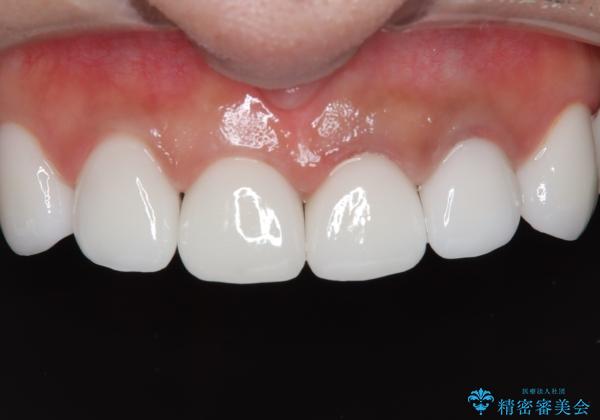

【オールセラミッククラウン】前歯を白くきれいにしたい。

- 前歯の変色を主訴に来院されました。

歯茎のラインも整っていなかったため、手術を行いきれいな被せ物をいれることができました。

歯茎のラインを整える手術を行ったあとは、しばらく待ってから被せ物の治療を行っていきます。